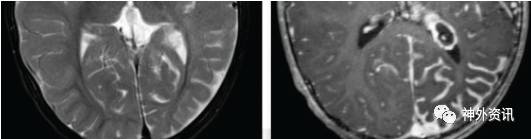

图18. 右侧的半球间纤维离断术的步骤如图所示。第一行所示图片展示了颞叶切除术,通过C形的皮层切除,打开侧脑室顶部,在胼胝体膝部切除的初始阶段确认了胼周动脉。中间一行图则显示通过使用左侧大脑镰和右侧天幕作为解剖标记来完成胼胝体压部的纤维离断术。下方的一行图则显示通过使用蝶骨嵴和床突作为解剖标记来进行皮层下的额叶切除术(左侧图)。岛叶切除术完成(右侧图)。